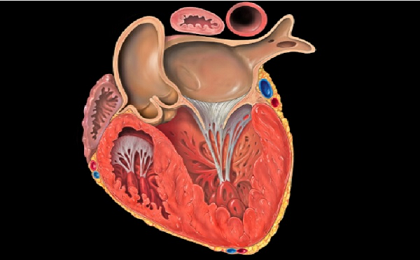

Một nghiên cứu mới, được công bố trên Tạp chí của Đại học Tim mạch Hoa Kỳ, nhấn mạnh việc sử dụng các thiết bị sức khỏe di động (mHealth) để giúp sàng lọc và phát hiện bệnh tim thông thường.